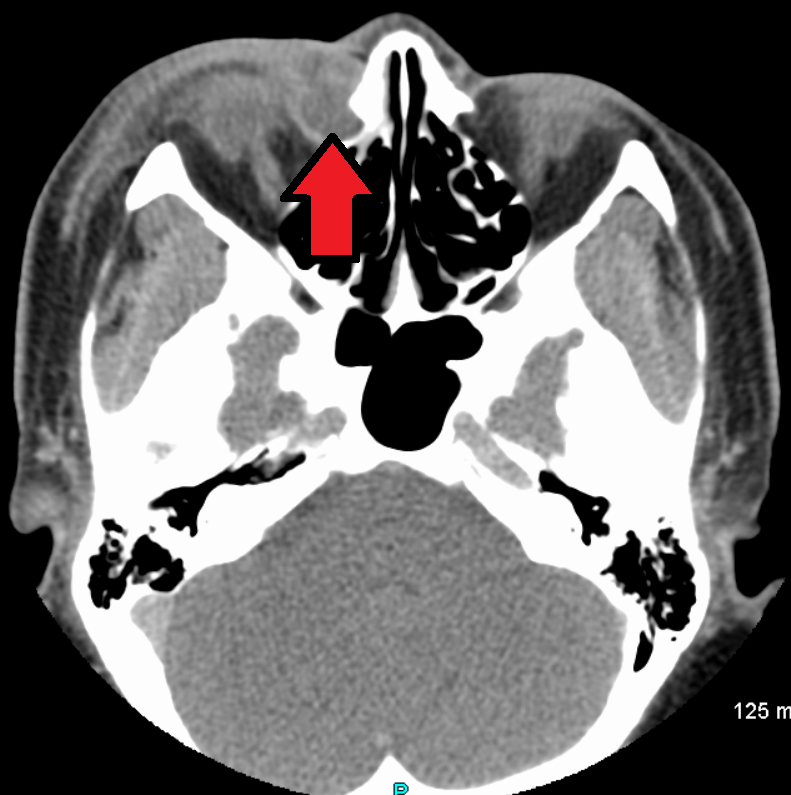

- CT: 안와 봉와직염 감별, 종양 의심 시